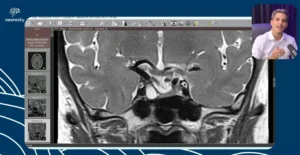

No vídeo "Coreia de Huntington: Achados na RM", o Dr. Tomás Freddi explora os aspectos neuroanatômicos e as características radiológicas da Doença de Huntington, uma desordem genética neurodegenerativa que afeta o controle motor e funções cognitivas. Esta condição é marcante por suas modificações nos gânglios da base e outras áreas cerebrais, as quais são bem evidentes em exames de ressonância magnética (RM). O vídeo é direcionado a profissionais e estudantes de saúde, com o objetivo de ampliar a compreensão sobre os achados em imagem e sua correlação clínica.

- Achados Radiológicos: Discussão acerca das alterações específicas observadas na ressonância magnética, como a atrofia dos gânglios da base.